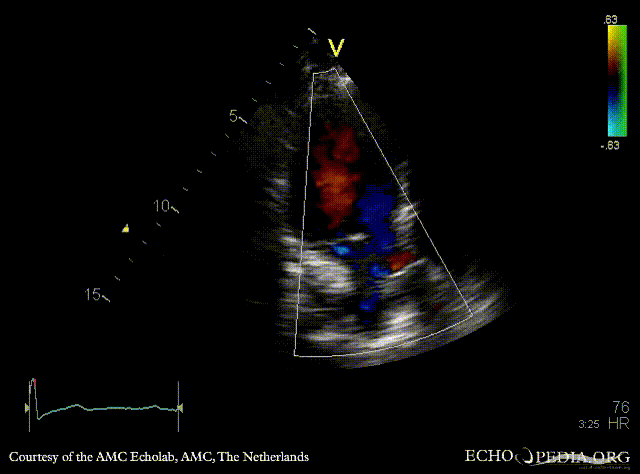

Subvalvular membrane

PSAX with Color Doppler: high velocity flow in LVOT A3CH: subvalvular membrane